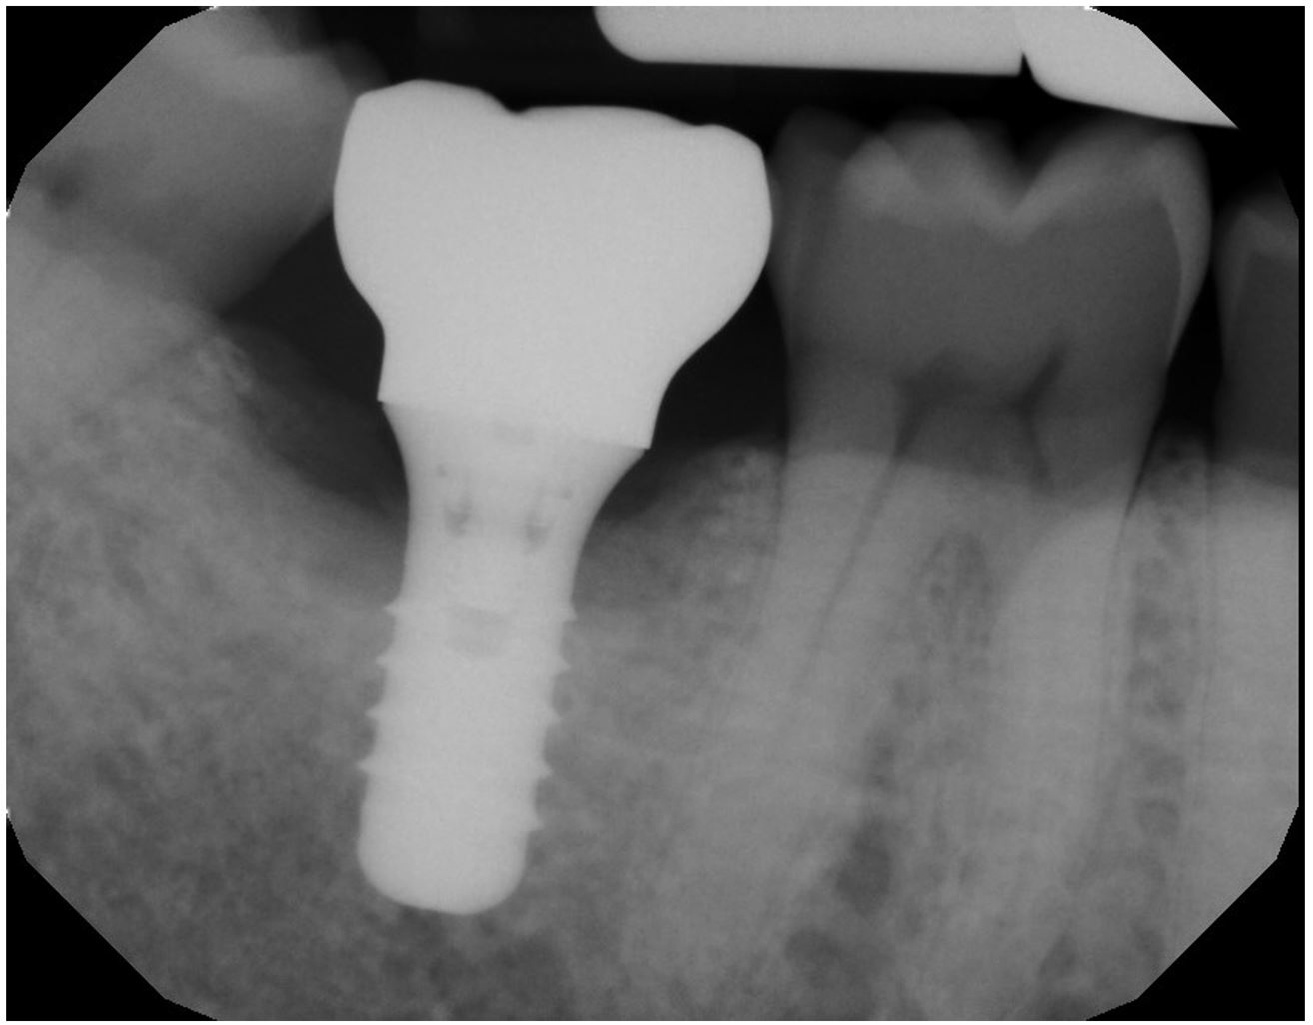

Laser for Periimplantitis

*Follow-up x-rays 9-12 months after treatment